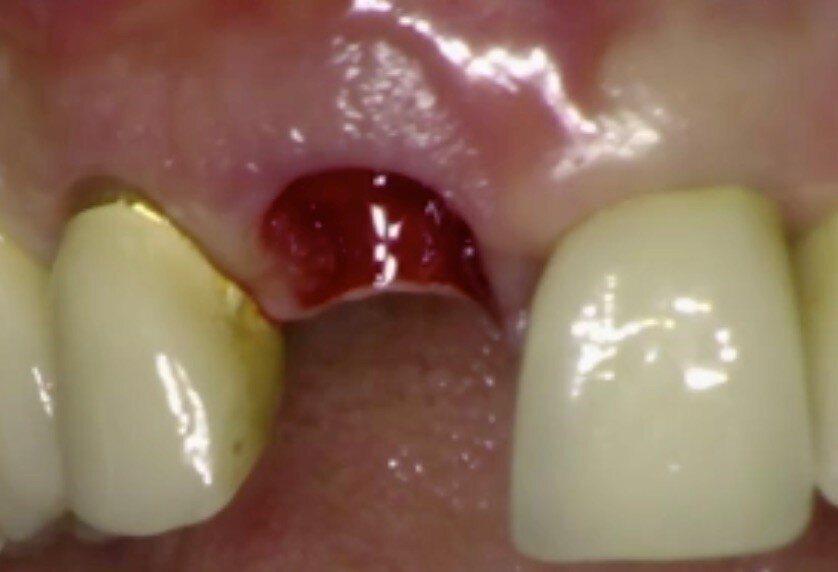

Le radiografie del caso completato nell’inizio del 2010 (Fig. 4) evidenziano la precisione del lavoro che è poi stato mantenuto nel corso degli anni. L’incisivo centrale destro 11 era stato trattato con apicectomia in passato ed era l’unico dente non vitale della riabilitazione. La paziente era seguita dal protesista che aveva portato a termine il caso. Nel 2021 la signora si è ripresentata con sintomatologia sul dente 21. Il lavoro eseguito nel 2010 era ancora in buone condizioni fatta eccezione per 11-12 ove 12 presentava una recessione gengivale con esposizione del collarino della cappetta galvanica che supportava la corona in ceramica e 11 presentava una piccola fistola nella sua porzione vestibolo distale (Figg. 5-7). La diagnosi era abbastanza semplice, l’11 aveva una frattura verticale e una prognosi infausta.

Nel caso in questione si pensò di utilizzare questa tecnica per favorire la possibilità alla paziente di avere un provvisorio immediato evitando di dovere intervenire con protesi mobili oppure andando a compromettere gli elementi adiacenti ancora ben funzionanti. La paziente venne pre-medicata con Ambramicina 250 mg (4 al dì) a partire da due giorni prima dell’intervento. Dopo aver somministrato l’anestesia locale con tecnica P-ASA6 utilizzando la Wand (Milestone) con articaina 1.200.000 l’elemento 21 veniva rimosso con molta cautela (Fig. 8). Il tessuto di granulazione presente all’apice rimosso con curettes, e l’alveolo post estrattivo disinfettato con H2O2 e Clorexidina 0.12%. La preparazione dell’intervento con conseguente carico immediato prevedeva l’uso di una mascherina chirurgica utile sia al posizionamento dell’impianto che alla successiva cementazione della corona provvisoria sull’impianto (Fig. 9). Il sito veniva preparato con le frese del caso ed era inserito un impianto Diagram (Schütz Dental) in posizione palatale (Fig. 10). Una volta inserita la fixture alla profondità e posizione corretta, con i bisturi da tunnelizazione veniva creato lo spazio vestibolarmente (laddove la frattura aveva completamente riassorbito la corticale) per l’inserzione di una lamina corticale ossea flessibile (Flex cortical sheet, Bioteck) dello spessore di 0.5 mm. La lamina veniva prima ritagliata (Fig. 11) poi idratata con soluzione fisiologica sterile per circa 30 secondi, ed infine inserita in posizione (Fig. 12).